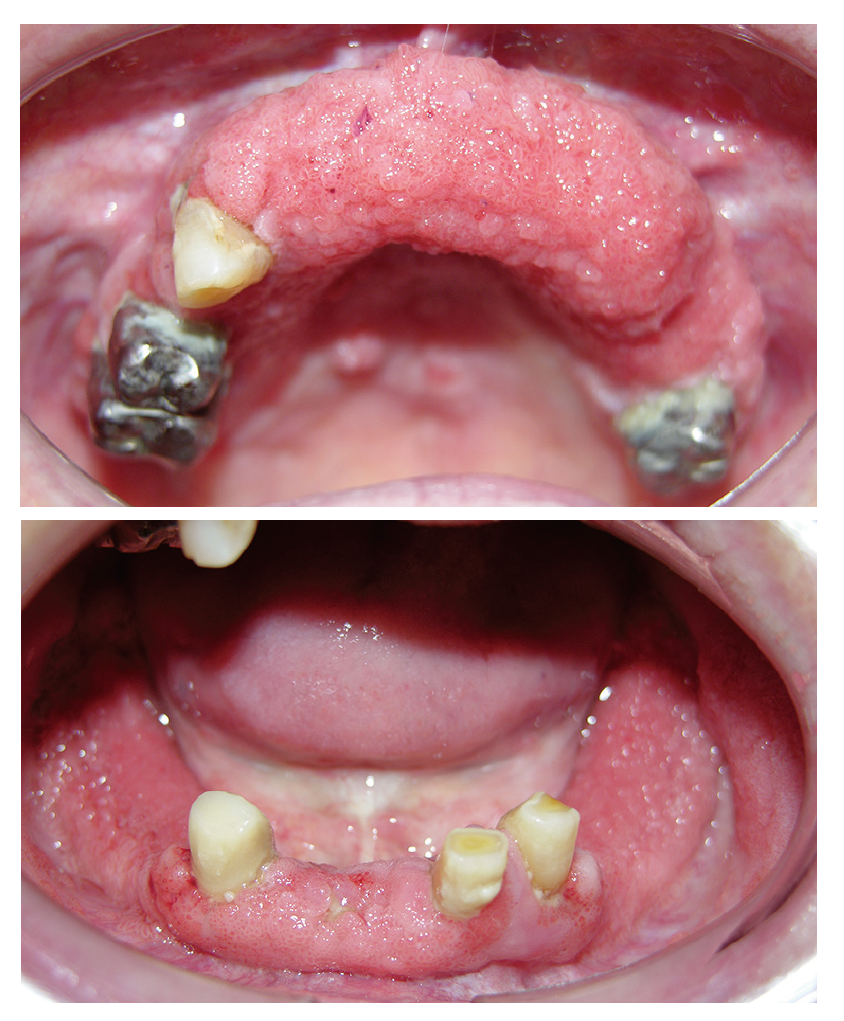

口腔内所見としては上顎犬歯間歯槽部、下顎全顎に及ぶ歯槽部、上唇内側粘膜に帯状で乳頭腫状に隆起した粘膜病変を認める(図1)。易出血性ではなく、圧痛などの症状もない。また、所属リンパ節の腫脹はない。